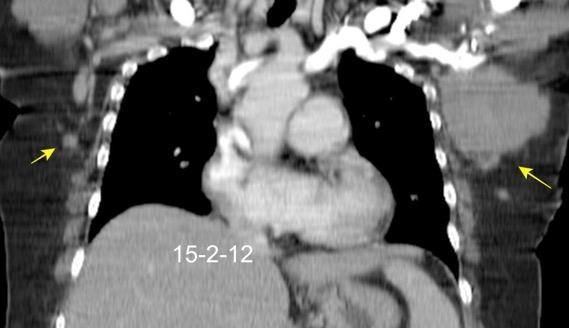

Masa axilar izquierda y derrame pleural derecho. Implantes pleurales, paraespinales . Ganglios en mamaria interna. Linfoma B difuso

Jaffe ES. Diagnosis and Classification of Lymphoma: Impact of Technical Advances.

2005. Masa pulmonar.

Linfoma NH de cél. B. Invasión Transtorácica.

Afectación axilar